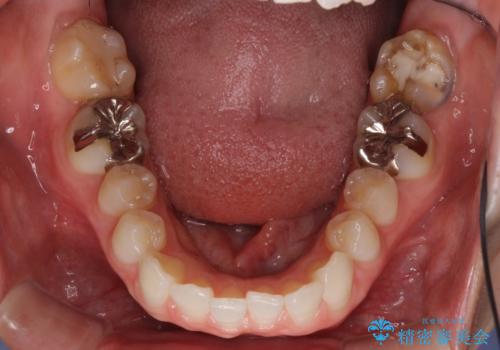

- 奥歯の虫歯と前歯のデコボコや突出感を気にして来院された患者様です。

上顎歯列が、下顎に対して前方にありましたが、口元に出っ歯の印象がなかったため、親知らずを抜歯した上で、上顎歯列全体を後方に移動させることとしました。

咬合力が強いため、アンカースクリューを使用し、ワイヤー装置にて矯正治療を行うこととしました。

矯正治療後は、奥歯の虫歯や銀歯を補綴・修復治療することとしました。